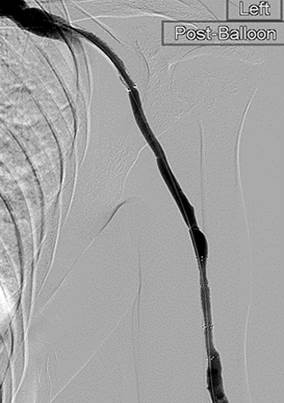

Post 2nd pass with DVX Catheter and balloon angioplasty of underlying stenosis. No impedance to forward flow in AVF.

Once forward flow is established and stenosis treated, the residual thrombus should resolve.